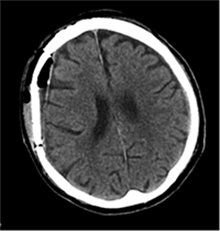

Po 2 savaičių pacientas rastas parkritęs kieme. Buvo matyti kraujuojanti žaizda. Pacientas pakartotinai hospitalizuotas į Neurochirurgijos skyrių. Atlikus GKT, nustatyta 25 mm storio hipodencinė juosta virš dešiniojo smegenų pusrutulio ir 8 mm vidurinių smegenų struktūrų dislokacija (VSD) į kairę (3 pav.). Įtariant lėtinę SDH dešinėje pusėje, pacientas reoperuotas, atliekant rekraniotomiją. Operacijos metu ant kietojo smegenų dangalo (KSD) rasta fibrino, jis pašalintas. Pravėrus KSD, rastas drumstas turinys, nesant aiškių pūlių, ir stora kapsulė. Gausiai praplauta šiltu fiziologiniu tirpalu subduraliai. Kaulinis lopas grąžintas (4 pav.). Po operacijos pacientas pradėjo skųstis stipriu galvos skausmu, tapo vangus. GKT pakartota. Įtarta empiema, nustatyti oro tarpai subduraliai, galvos smegenų VSD – 6 mm. Praėjus 12 dienų po antros operacijos, pacientas operuotas pakartotinai. Operacijos metu atlikta rekraniotomija. Epiduriniame ir subduriniame tarpuose rasta pūlių ir fibrino. Pūliai ir fibrinas pašalinti, paimtas bakteriologinis pasėlis. Žaizda gausiai praplauta šiltu fiziologiniu tirpalu. Kaulinis lopas negrąžintas, minkštieji audiniai susiūti (5 pav.). Po operacijos paciento būklė stabilizavosi. Bakteriologiniame pasėlyje negausiai užaugo E. coli, jautri ampicilinui. Nesant teigiamo efekto gydant ampicilinu, dar 2 savaites pacientui skirta gentamicino. Praėjus 3 savaitėms po trečios operacijos, pacientas perkeltas į slaugos ligoninę palaikomojo gydymo.

3 pav. Prieš antrąją operaciją (25 mm storio hipodencinė juosta virš dešiniojo smegenų pusrutulio, esant 8 mm dislokacijai į kairę; įtarta lėtinė SDH dešinėje)